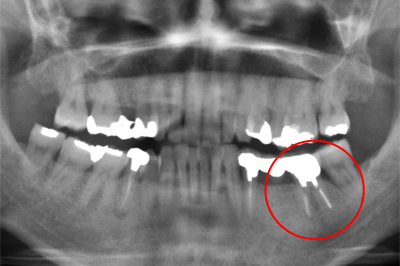

インプラント施術例

歯を削りたくない、入れ歯をどうしても入れたくないという時、インプラント治療を行っています。

レントゲン